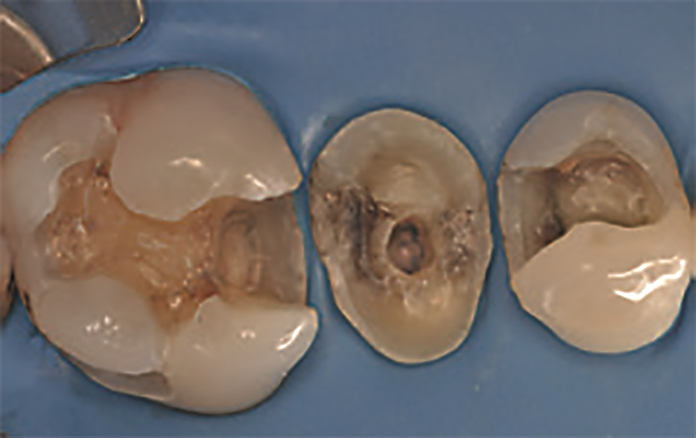

Na drugiej wizycie pacjentka poprosiła o estetyczną wymianę dwóch wypełnień amalgamatowych na zębach 16 i 14. Po doborze koloru wypełnienia uzyskano izolację pola zabiegowego za pomocą koferdamu OptiDam™ (Kerr). Wypełnienia amalgamatowe zostały usunięte pod obfitym strumieniem wody (ryc. 4). Procedura adhezyjna w zębie 16 została przeprowadzona za pomocą OptiBond Universal, z zastosowaniem protokołu wytrawiania total‑etch. Po nałożeniu formówki Adapt SuperCap Matrix (Kerr), opracowanej specjalnie do dużych uzupełnień w odcinku bocznym, na całą opracowaną wcześniej powierzchnię zęba nałożono żel zawierający 37,5% kwasu ortofosforowego (Gel Etchant, Kerr) (ryc. 5). Po 15 sekundach ubytek został dokładnie wypłukany, a następnie osuszony delikatnym strumieniem powietrza. Takie postępowanie zapobiega zapadnięciu się włókien kolagenowych, co skutkowałoby ograniczeniem infiltracji systemu łączącego.